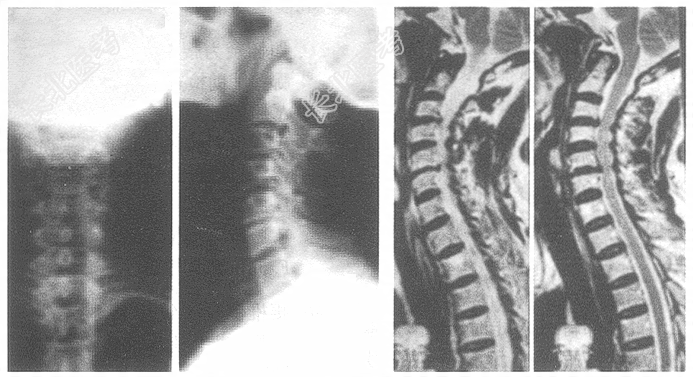

- 多项选择题3.根据以上资料,最有可能的诊断是(提示: X线片、MRI见图。)

G、后纵韧带骨化